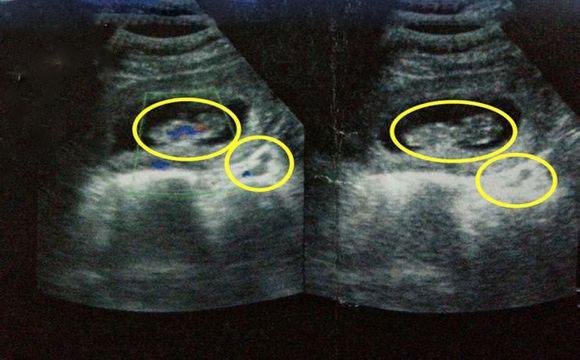

首先我们需要先了解一下龙凤胎是怎么形成的?在科学上来说龙凤胎就是一男一女,是异卵双胞胎,这是需要女方的同时排出两个卵子,女人一个月只排出一个卵子,要排出两个卵子,那真的是有拼运气了,2个卵子分别授精就形成龙凤胎了。

首先我们需要先了解一下龙凤胎是怎么形成的?在科学上来说龙凤胎就是一男一女,是异卵双胞胎,这是需要女方的同时排出两个卵子,女人一个月只排出一个卵子,要排出两个卵子,那真的是有拼运气了,2个卵子分别授精就形成龙凤胎了。

而且龙凤胎的几率比双胞胎还要小,先不说龙凤胎好不好,你就是想要怀上龙凤胎都是难如登天,比买彩票一样中奖的可能性还小。不过这个也是要受到遗传因素的影响的,要是母亲这边有生龙凤胎,就算是隔几代也是有可能会生龙凤胎的,当然母亲生龙凤胎,下一代生龙凤胎的概率是最大的,会增加到1.7%

而且龙凤胎的几率比双胞胎还要小,先不说龙凤胎好不好,你就是想要怀上龙凤胎都是难如登天,比买彩票一样中奖的可能性还小。不过这个也是要受到遗传因素的影响的,要是母亲这边有生龙凤胎,就算是隔几代也是有可能会生龙凤胎的,当然母亲生龙凤胎,下一代生龙凤胎的概率是最大的,会增加到1.7%